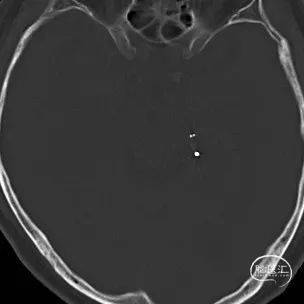

术后CT提示支架打开良好。

术前CT